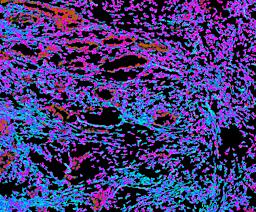

Pancreatic ductal adenocarcinoma is a lethal disease with limited treatment options and poor survival. We studied 83 spatial samples from 31 patients (11 treatment-naïve and 20 treated) using single-cell/nucleus RNA sequencing, bulk-proteogenomics, spatial transcriptomics and cellular imaging. Subpopulations of tumor cells exhibited signatures of proliferation, KRAS signaling, cell stress and epithelial-to-mesenchymal transition. Mapping mutations and copy number events distinguished tumor populations from normal and transitional cells, including acinar-to-ductal metaplasia and pancreatic intraepithelial neoplasia. Pathology-assisted deconvolution of spatial transcriptomic data identified tumor and transitional subpopulations with distinct histological features. We showed coordinated expression of TIGIT in exhausted and regulatory T cells and Nectin in tumor cells. Chemo-resistant samples contain a threefold enrichment of inflammatory cancer-associated fibroblasts that upregulate metallothioneins. Our study reveals a deeper understanding of the intricate substructure of pancreatic ductal adenocarcinoma tumors that could help improve therapy for patients with this disease.